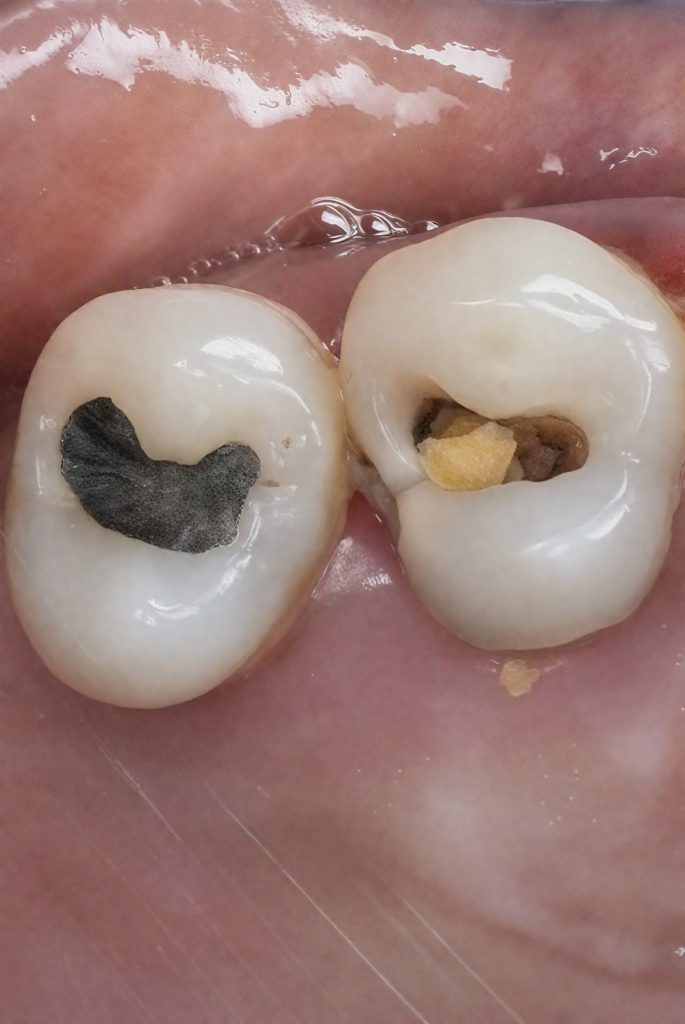

This case demonstrates the complete management of a maxillary premolar with irreversible pulpitis and compromised coronal structure. The treatment involved root canal therapy under rubber dam isolation, followed by adhesive restoration to ensure functional and esthetic rehabilitation.

3. Access Opening & Pulpal Exposure